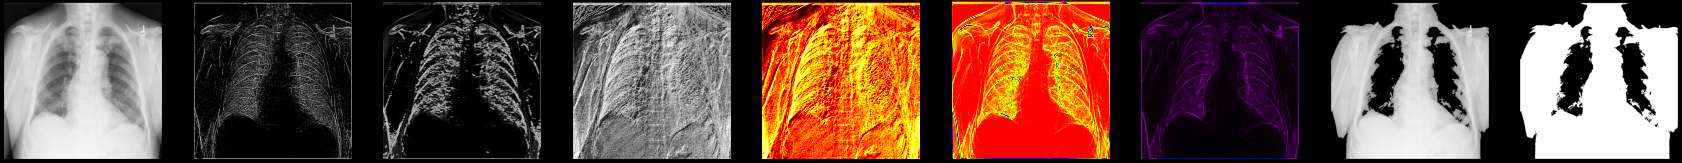

让我们显示一些您迄今为止处理过的 X 射线图像的结果:

fig, axes = plt.subplots(nrows=1, ncols=9, figsize=(30, 30))

axes[0].set_title("Original")

axes[0].imshow(xray_image, cmap="gray")

axes[1].set_title("Laplace-Gaussian (edges)")

axes[1].imshow(xray_image_laplace_gaussian, cmap="gray")

axes[2].set_title("Gaussian gradient (edges)")

axes[2].imshow(x_ray_image_gaussian_gradient, cmap="gray")

axes[3].set_title("Sobel (edges) - grayscale")

axes[3].imshow(xray_image_sobel, cmap="gray")

axes[4].set_title("Sobel (edges) - hot")

axes[4].imshow(xray_image_sobel, cmap="hot")

axes[5].set_title("Canny (edges) - prism)")

axes[5].imshow(xray_image_canny, cmap="prism")

axes[6].set_title("Canny (edges) - nipy_spectral)")

axes[6].imshow(xray_image_canny, cmap="nipy_spectral")

axes[7].set_title("Mask (> 150, noisy)")

axes[7].imshow(xray_image_mask_noisy, cmap="gray")

axes[8].set_title("Mask (> 150, less noisy)")

axes[8].imshow(xray_image_mask_less_noisy, cmap="gray")

for i in axes:

i.axis("off")

plt.show()